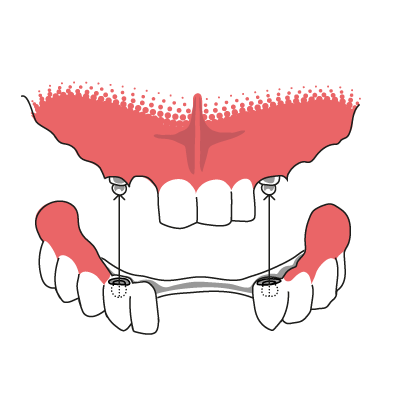

Druckknopfprothese auf Kronen